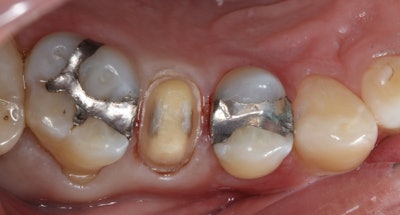

The existing mesio-occluso-distal (MOD) amalgam restoration on tooth #4 exhibited leakage and recurring decay, as evidenced by radiographic findings. Cold sensitivity that did not linger longer than five seconds was confirmed on the cervical margin of tooth #4, and the heat and percussion tests were negative.

Adjacent teeth #3 and #5 also displayed failing amalgam restorations. The Tooth Sleuth device identified a cracked buccal cusp on tooth #4, and cervical abfractions were observed on the posterior teeth.